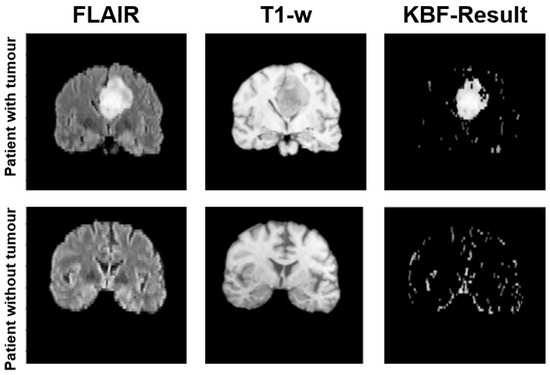

4.2. Knowledge-Based Filtering (KBF)